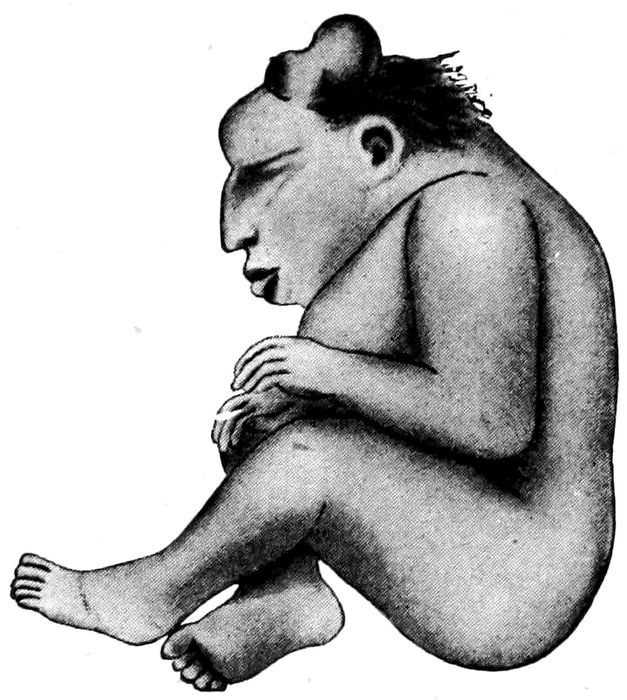

The Mature Fœtus.—Although subject to considerable

variation, the fœtus at term will weigh about seven and

one-fourth pounds, and measure 50 cm. in length. The

weight is far more uncertain than the length, and therefore

not so reliable as a sign of maturity.

Differences between the mature and immature

fœtus:

| Mature |

Immature |

| |

| 1. |

Skin smooth, plump, pink covered with vernix caseosa. |

1. |

Skin lax, wrinkled, dull red in color; little vernix caseosa. |

| |

| 2. |

Generous amount of subcutaneous fat. |

2. |

Subcutaneous fat scanty. |

| |

| 3. |

Hair abundant and from 1 to 2 inches long. |

3. |

Hair on scalp short. |

| |

| 4. |

Lanugo mostly absent. |

4. |

Lanugo present all over body. |

| |

| 5. |

Nails project from finger tips. |

5. |

Short nails on fingers and toes. |

| |

| 486. |

Skull bones in contact except at fontanelles. |

6. |

Skull sutures open. |

| |

| 7. |

Length 50 cm. born. |

7. |

Moves and cries feebly when |

| |

| 8. |

Weight five to eight pounds. |

8. |

Weight less than five pounds. |

| |

| 9. |

Cartilage in ear well developed. |

|

|

| |

| 10. |

Navel in middle of body. |

|

|

| |

| 11. |

Testes have descended in the male, and the labia majora in the female usually cover the labia minora. |

|

|

| |

| 12. |

Moves and cries vigorously when born. |

|